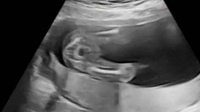

子宮がみえる さらに大きく成長すると、赤ちゃんの体内の臓器も確認できるようになっていきます。 胃や膀胱などは男の子にもみえますが、 子宮がみえるのは女の子だけです 。赤ちゃんの下腹部に黒い丸いのが2つ見えました。1つは膀胱炎にしても、もう1つは?性 膀胱癌とエコー像(Bladder cancer and the echo images) 膀胱癌の背景、原因、特徴、検査法、病理像、エコー像についてまとめました。 エコーで見ると、赤ちゃんの体には黒くて丸い点が写ります。 男の子の場合、それは膀胱で点は一つだけですが、 女の子は、膀胱と子宮が点となって見える のです。

赤ちゃんの目鼻立ちなどもわかるので感動するパパママは多いです! 妊娠初期のエコー写真を見てみよう! 妊娠初期に医師は超音波検査にて主に5つのポイントを確認しています。 その1 子宮内で正常に妊娠しているか; 妊娠22週目の女の子のエコー写真 右上がおしり、左下に向かって2本の足が生えています。 こちらはコーヒー豆や葉っぱのような割れ目(シンボル)のようなものが見えるのが分かりやすい写真です。 妊娠25週目の女の子のエコー写真 この頃になると 女の子の赤ちゃんは、子宮と膀胱が2つの黒い点となって見えます 。 一方、男の子は子宮がないため黒い点は1点のみです。 しかしモノクロのエコー画像では黒い点がどこにあるのかわかりにくいので、先生に尋ねてみることをおすすめします。